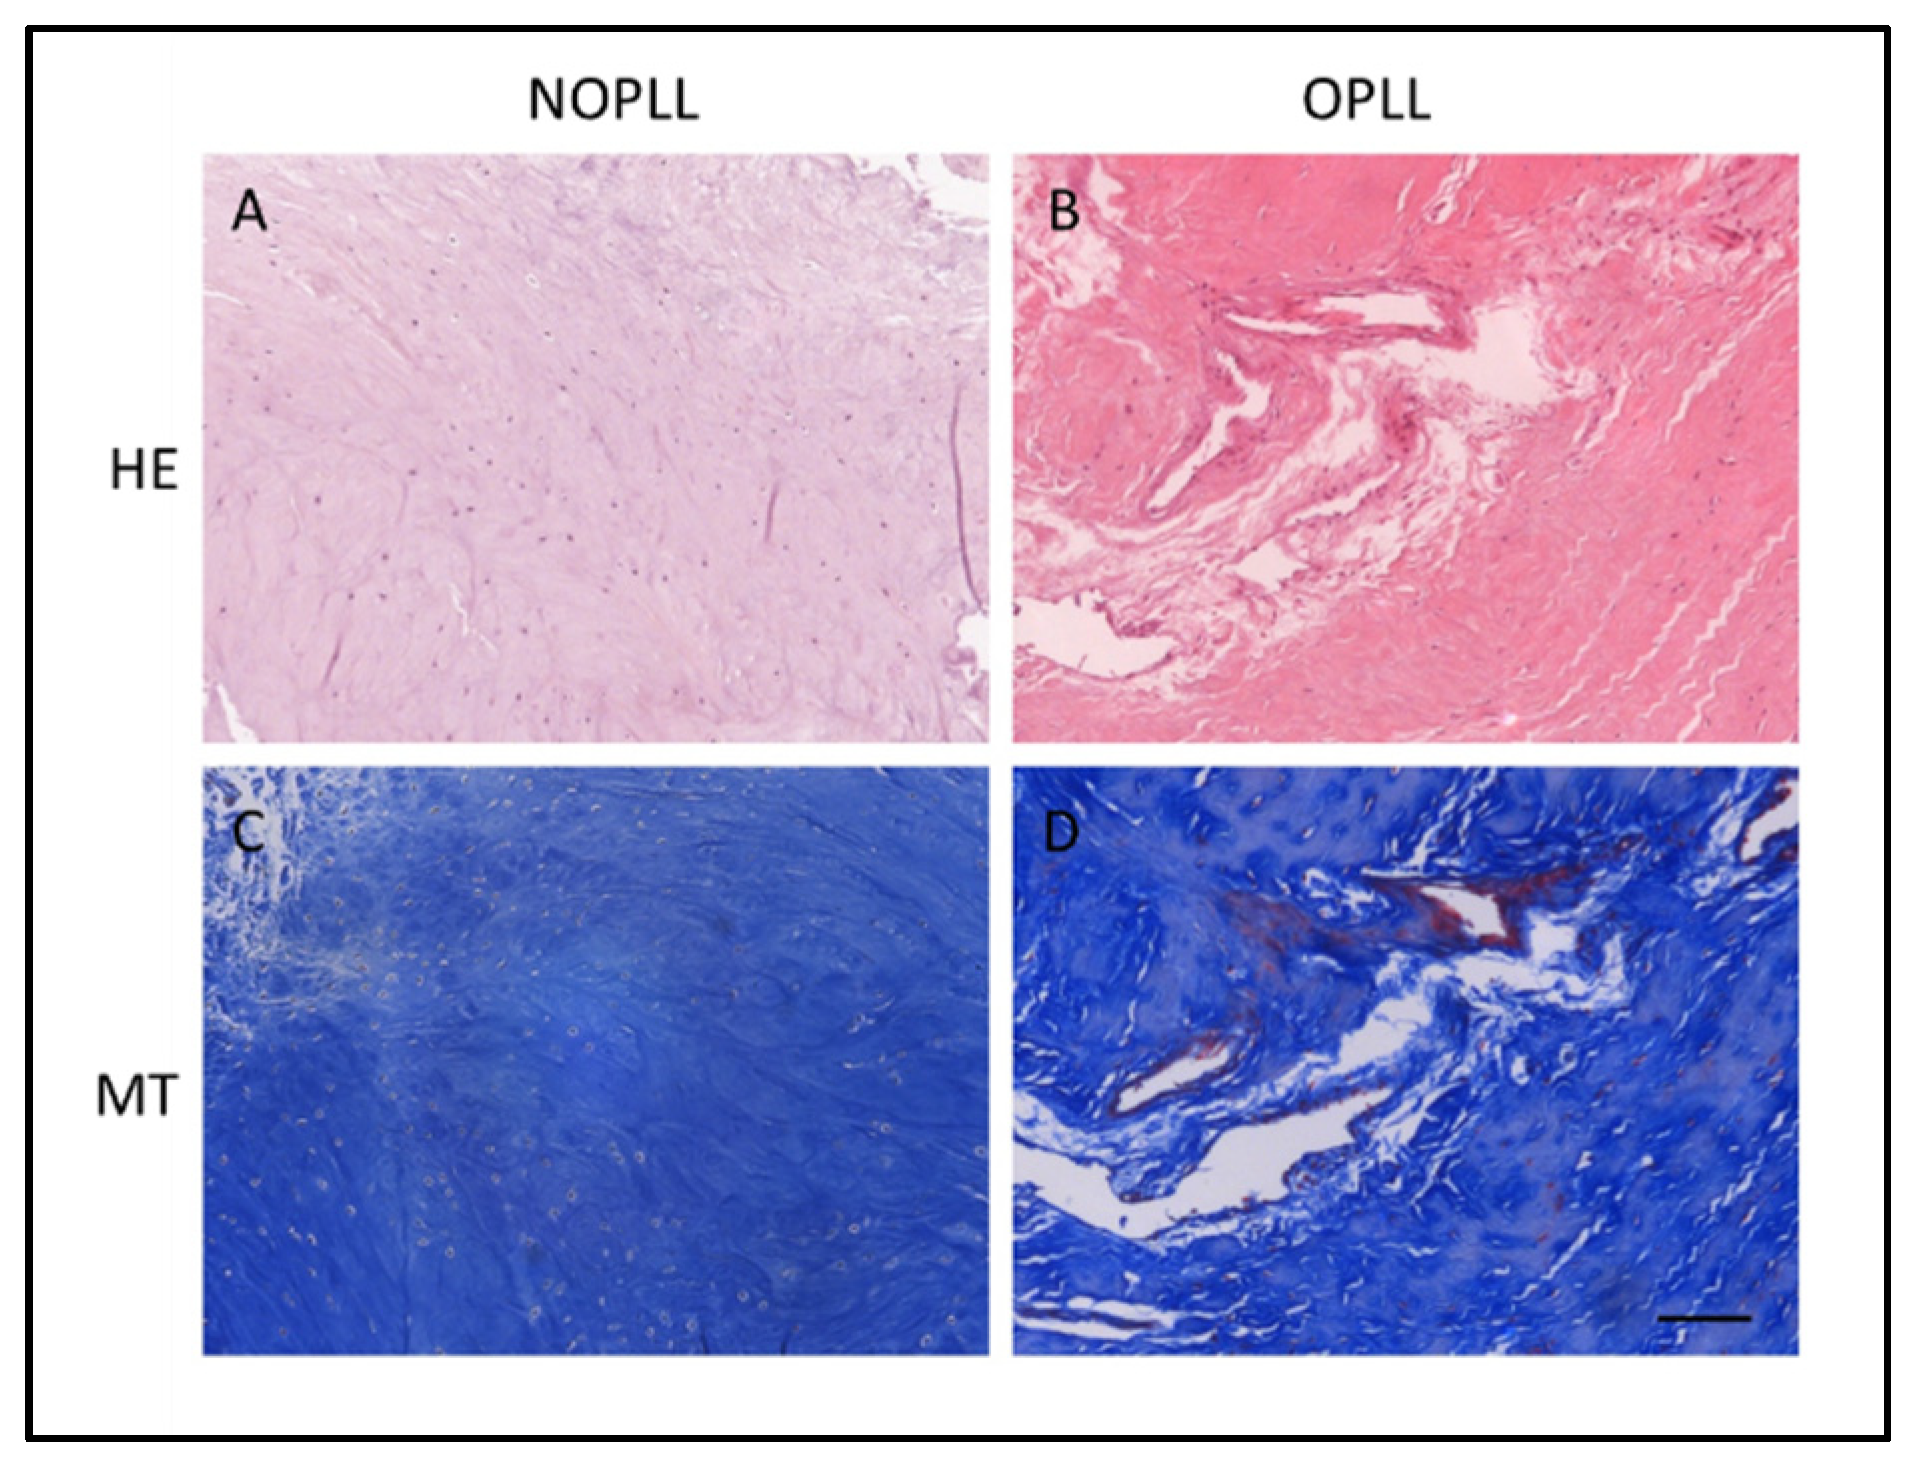

2.3. Histologic Examination

3.2. Histological Staining